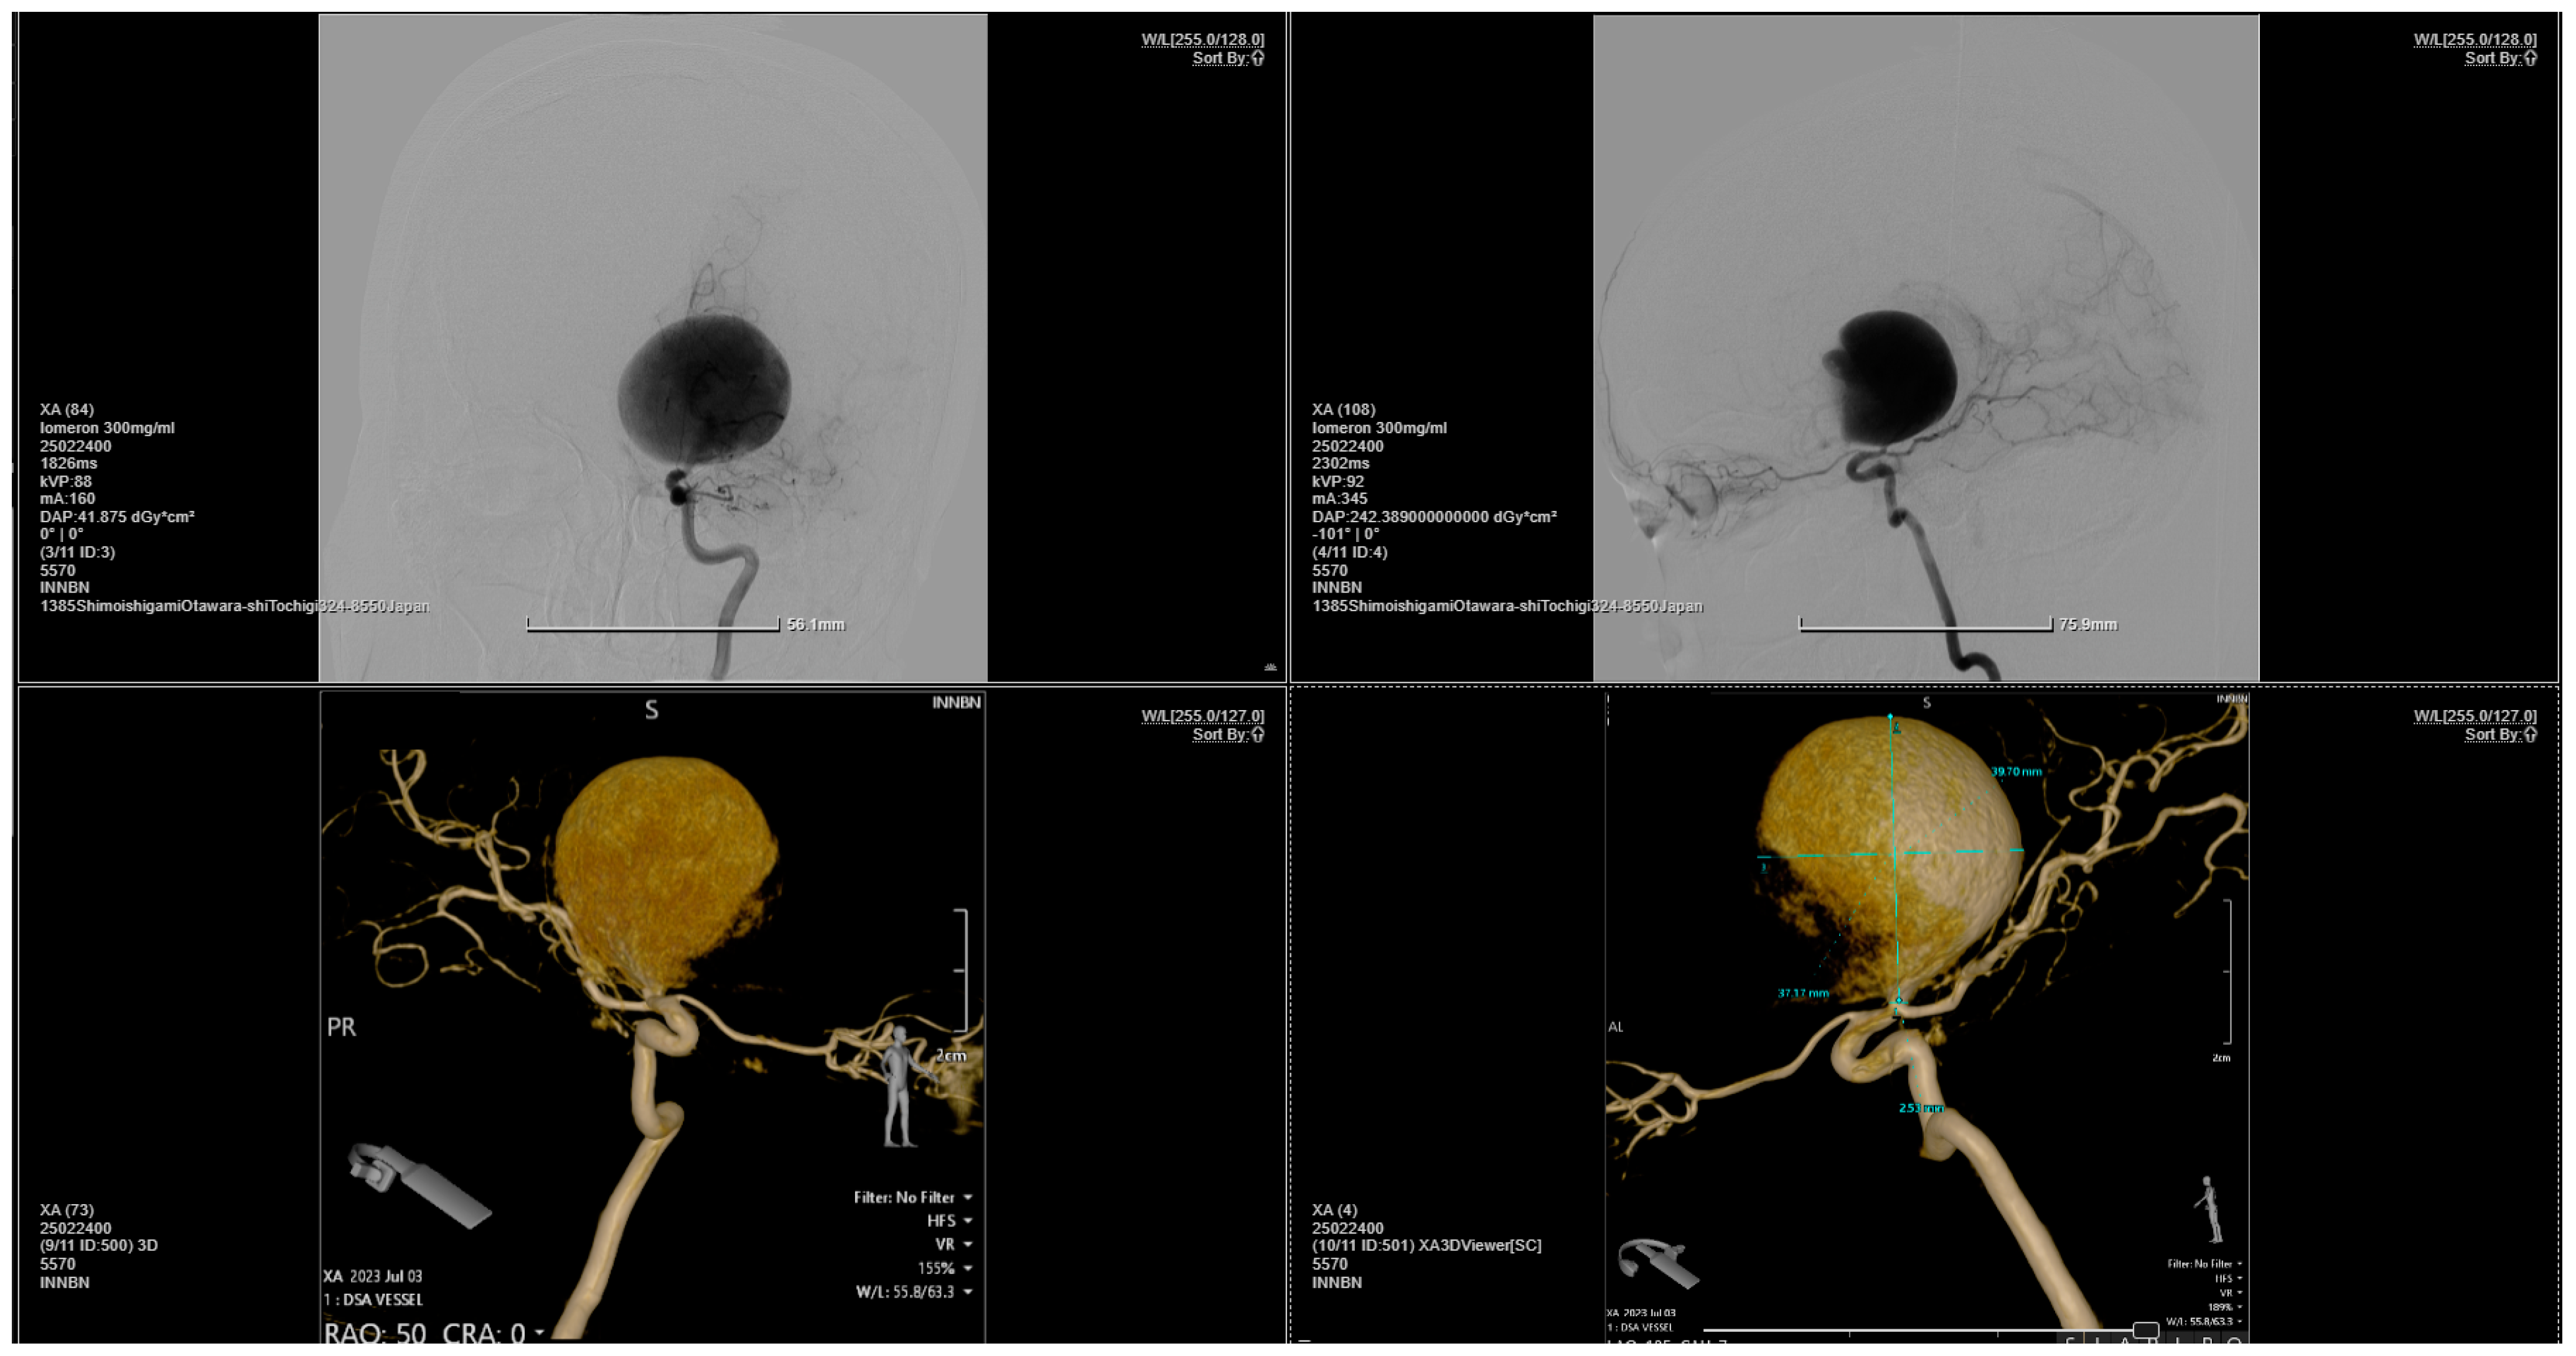

Figure 2.

Bilateral carotid and vertebral angiography reveals a giant aneurysm located at the bifurcation of the right internal carotid artery, encompassing the M1 segment of the right middle cerebral artery. The right middle cerebral artery is not injected. Otherwise, the main arterial vessels of the brain appear normal.

Figure 3.

The 3D reconstruction of the rotational DSA illustrating a giant aneurysm with dimensions of 4 × 3.75 cm, located at the bifurcation of the right internal carotid artery, encompassing the M1 segment of the right middle cerebral artery.